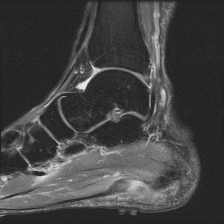

Object Movement

MRI OmniMedVQA Disease Diagnosis

Object Movement - L0 (Original)

L0

L0 (Original)

Object Movement - L1 (Moderate)

L1

L1 (Moderate)

Object Movement - L2 (Severe)

L2

L2 (Severe)

Question

What is the visual finding in this image?

A Rotator cuff tear B Plantar fascia pathology C Bunion D Golfer's elbow

Ground Truth: B. Plantar fascia pathology